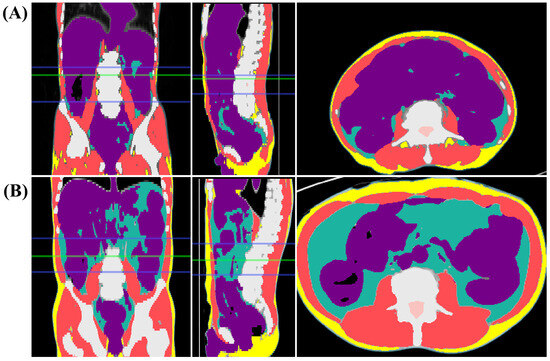

2.2. Assessment of Sarcopenia

- Kim, M.; Lee, S.M.; Son, I.T.; Park, T.; Oh, B.Y. Prognostic value of artificial intelligence-driven, computed tomography-based, volumetric assessment of the volume and density of muscle in patients with colon cancer. Korean J. Radiol. 2023, 24, 849–859. [Google Scholar] [CrossRef]

- Han, Q.; Kim, S.I.; Yoon, S.H.; Kim, T.M.; Kang, H.C.; Kim, H.J.; Cho, J.Y.; Kim, J.W. Impact of computed tomography-based, artificial intelligence-driven volumetric sarcopenia on survival outcomes in early cervical cancer. Front. Oncol. 2021, 11, 741071. [Google Scholar] [CrossRef]

- Lee, Y.S.; Hong, N.; Witanto, J.N.; Choi, Y.R.; Park, J.; Decazes, P.; Eude, F.; Kim, C.O.; Chang Kim, H.; Goo, J.M.; et al. Deep neural network for automatic volumetric segmentation of whole-body CT images for body composition assessment. Clin. Nutr. 2021, 40, 5038–5046. [Google Scholar] [CrossRef] [PubMed]

- Weston, A.D.; Korfiatis, P.; Kline, T.L.; Philbrick, K.A.; Kostandy, P.; Sakinis, T.; Sugimoto, M.; Takahashi, N.; Erickson, B.J. Automated abdominal segmentation of CT scans for body composition analysis using deep learning. Radiology 2019, 290, 669–679. [Google Scholar] [CrossRef] [PubMed]

- Kim, S.I.; Chung, J.Y.; Paik, H.; Seol, A.; Yoon, S.H.; Kim, T.M.; Kim, H.S.; Chung, H.H.; Cho, J.Y.; Kim, J.W.; et al. Prognostic role of computed tomography-based, artificial intelligence-driven waist skeletal muscle volume in uterine endometrial carcinoma. Insights Imaging 2021, 12, 192. [Google Scholar] [CrossRef] [PubMed]